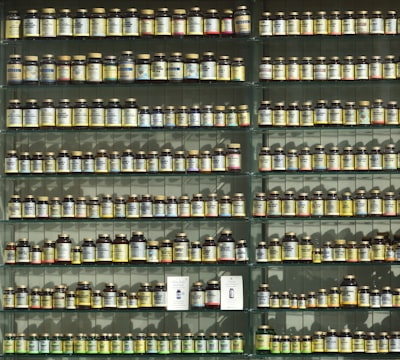

Pain medicine includes a wide range of drugs meant to reduce pain. These analgesic drugs work in different ways. They often target pain receptors or block pain signals in the nervous system. The main goal of pain management is to ease suffering and help people function better. This allows them to do daily activities and improve their quality of life.

Topical Analgesics for pain managment medicines opioid, cannabinoids and antidepressants

Today, we have many options for pain management. Each medicine works in its own way and is used for different reasons, considering potential adverse effects. Over-the-counter choices like acetaminophen (Tylenol) and ibuprofen are good for mild to moderate pain and inflammation. For more serious pain, like after surgery or during cancer pain, opioids such as oxycodone and fentanyl are used.

Common pain medicines are:

- NSAIDs, like ibuprofen

- COX-2 inhibitors to reduce inflammation

- Muscle relaxants for calming spasms

- Lidocaine patches for pain relief in one area